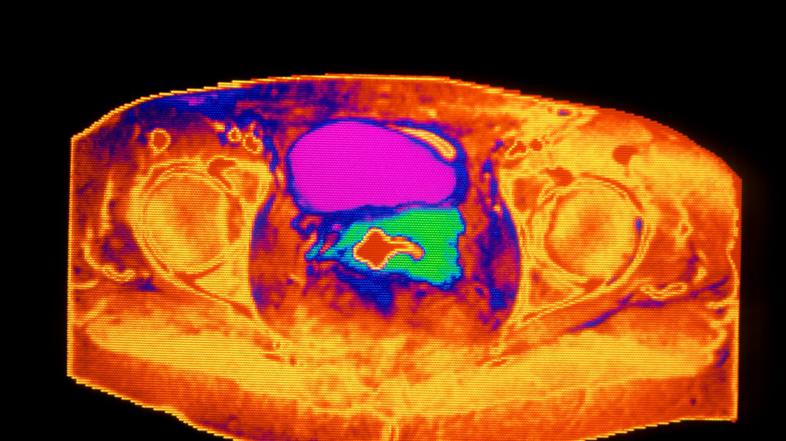

Profimedia